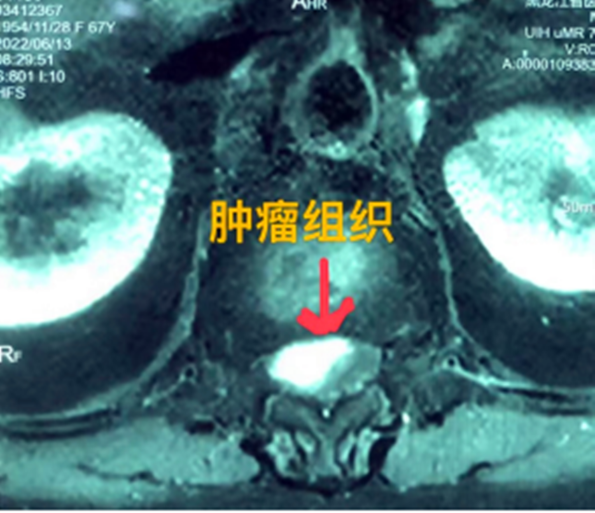

四公分大脊髓腫瘤充滿髓腔完全壓迫神經(jīng)

黑龍江經(jīng)濟(jì)網(wǎng)訊(林穎 董宇翔 梁新立) 近日,黑龍江省醫(yī)院收治了一名胸椎管內(nèi)腫瘤患者,該患者為少見的脊髓腫瘤,腫瘤長度達(dá)到四公分,充滿髓腔且神經(jīng)已經(jīng)完全受壓。最終,省醫(yī)院神經(jīng)外一科專家和骨外一科專家團(tuán)結(jié)協(xié)作,共同完成了這臺高難度腫瘤切除術(shù),患者現(xiàn)已順利康復(fù)出院。

據(jù)省醫(yī)院神經(jīng)外一科陶宇醫(yī)生介紹,家住外地的張大娘最近總感覺雙下肢疼痛、無力,且排尿困難及便秘,伴有行走困難。時間長了,張大娘病情逐漸加重,劇烈的疼痛甚至讓她無法完整入睡。在當(dāng)?shù)蒯t(yī)院,張大娘按腰椎肩盤突出接受治療,但未見好轉(zhuǎn),隨后進(jìn)行的胸椎MRI(核磁共振)檢查,結(jié)果不禁讓張大娘和家屬瞠目結(jié)舌,原來張大娘患的竟然是少見的脊髓腫瘤。

張大娘住進(jìn)了黑龍江省醫(yī)院神經(jīng)外一科,該科孫國章主任醫(yī)師熱情地接待了張大娘,并邀請骨外一科專家共同為她進(jìn)行了聯(lián)合會診。發(fā)現(xiàn)張大娘病情十分復(fù)雜棘手,脊髓腫瘤體積較大,充滿髓腔且神經(jīng)已經(jīng)完全受壓,需要手術(shù)來完整切除。同時還發(fā)現(xiàn)張大娘的胸腰部曾受過兩次外傷,伴有多處骨折,這對接下來的手術(shù)操作帶來一定影響。